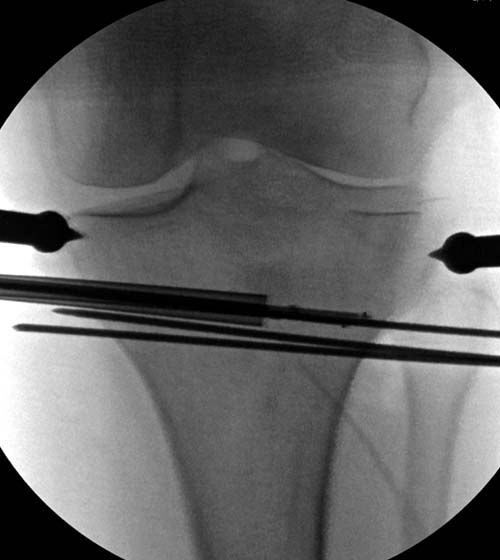

Для лечения некоторых видов центральной импрессии (Schatzker III) можно применить методику Balloon tibioplasty, которая позволяет приподнять сустав без дополнительных доступов. Для информации здесь недавний пример, дефект заполнен жидкой формой композитного материала PRO-DENSE: http://www.wmt.com/prodense/product_overview.asp